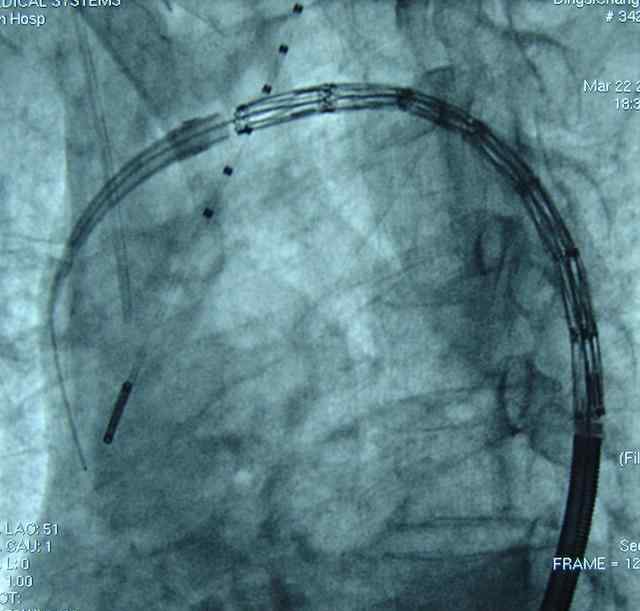

患者病情适当稳定后,治疗方式的选择主要取决于解剖类型。目前,微创血管内治疗是斯坦福B型主动脉夹层的主要治疗方法。

主动脉夹层微创血管内修复术是通过混合手术或各种血管内修复技术(烟囱、开窗、模块化分支支架)治疗距左锁骨下动脉开口1.5cm以内的斯坦福B型主动脉夹层。

A型主动脉夹层是死亡率最高的动脉疾病,死亡率和并发症发生率较高。外科治疗的主要目标是挽救病人的生命。过去相对保守但最简单、最安全的治疗方法是简单地更换升主动脉或升主动脉的一部分,以消除原发性破裂,挽救生命。随着外科技术、麻醉、器官保护和术后护理的进步,主动脉手术中血管置换的范围逐渐扩大,从而降低了残余主动脉疾病并发症的发生率。目前斯坦福A型的杂交技术,早期采用手术和血管腔内人工血管植入的方法。